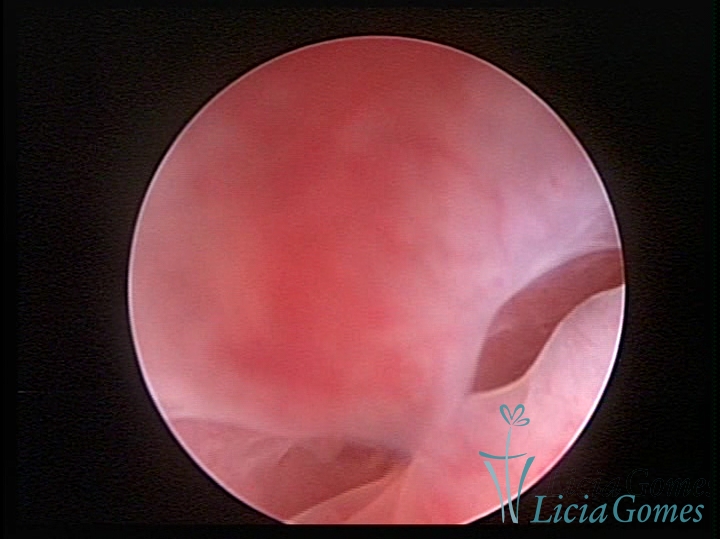

Sinéquia TIPO FIBROSA

• SINÉQUIA TIPO FIBROSA